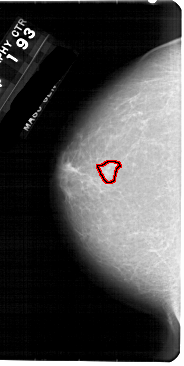

A_1948_1.LEFT_CC

LEFT_CC LINES 5476 PIXELS_PER_LINE 2746 BITS_PER_PIXEL 12 RESOLUTION 43.5 OVERLAY

FILE: A_1948_1.LEFT_CC.OVERLAY

TOTAL_ABNORMALITIES 1

ABNORMALITY 1

LESION_TYPE MASS SHAPE IRREGULAR MARGINS ILL_DEFINED

ASSESSMENT 4

SUBTLETY 3

PATHOLOGY BENIGN

TOTAL_OUTLINES 1

BOUNDARY